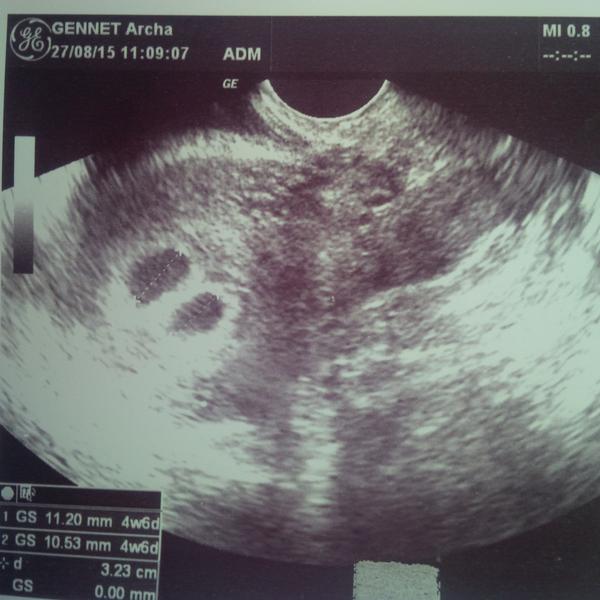

Tak výsledky už mám hcg 32642 🙂 🙂 🙂

Gratuluji, to je obrovská hodnota, to budou určitě dvojčátka!!! 😀

Hele vypadá to na dvojčátka 😉